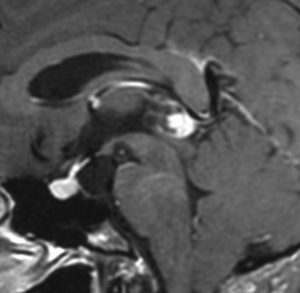

成人女性の松果体細胞腫で充実性腫瘍です。多少凹凸がありますがだいたい楕円形。中脳水道が閉塞して軽度の水頭症(頭の中に髄液が溜まる)になってきています。急性水頭症で急変して意識障害になることがありますので,迷わず摘出するか,第3脳室開窓術 ETVをしてから経過観察します。